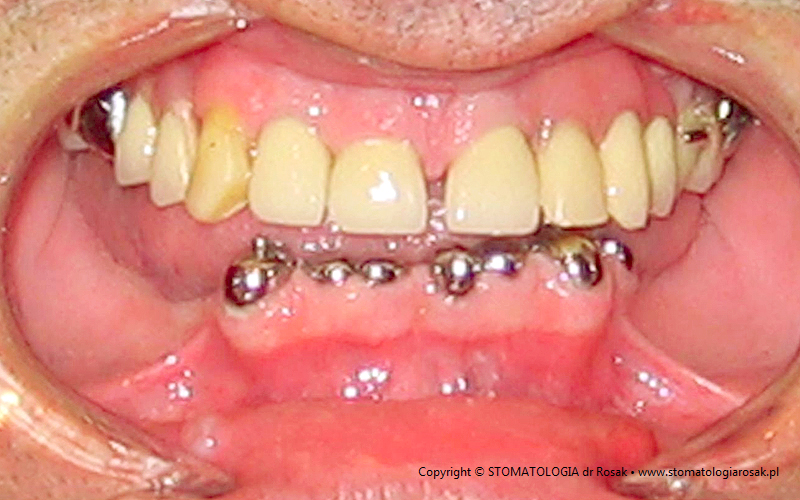

9. Pacjent lat 57- zgłosił się celem usunięcia zniszczonych zębów i wykonania protez ruchomych całkowitych.

NIE USUNĘLIŚMY - ANI JEDNEGO ZĘBA!!!

| 9a. Przed leczeniem |

9b. Gotowe korony i mosty porcelanowe na górze

(trójkę górną prawą pacjent zażyczył sobie nie korygować)

oraz w żuchwie tzw. czapeczki pokrywające oraz zatrzaski kulowe dla lepszego utrzymania protezy ruchomej dolnej |